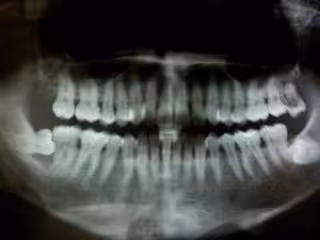

Investigan el vínculo entre la inflamación periodontal y la degeneración de la retina

Periodontitis

FLICKR/FELIX E. GUERRERO - Archivo